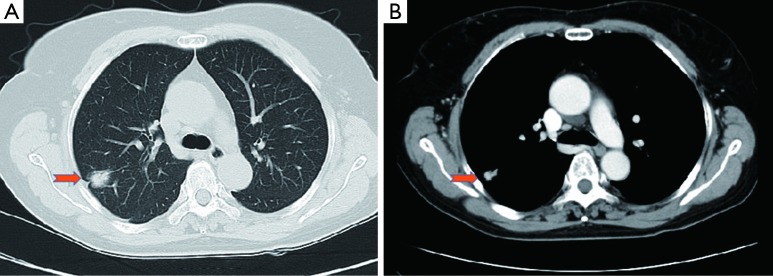

A 64-year-old female presented with a 2.0 cm × 2.0 cm × 1.0 cm nodule in posterior segment of right upper lobe and a ground glass opacity (GGO) in the left upper lobe on computed tomographic (CT) (Figures 1,2) was admitted in our institute on March 16th, 2014. The patient underwent preoperative staging and cardiac and pulmonary function assessment. PET-scan indicates no signs of metastasis. Under general anesthesia with double lumen tube, the patient underwent uniportal cVATS lobectomy for right upper lung tumor on March 19th, 2014 (Figure 3). The final pathologic TNM staging is T1aN0M0 (IA). Regular follow up was initiated for the GGO in the left upper lobe.

Figure 1.

(A,B) A shadow in the right upper lobe.